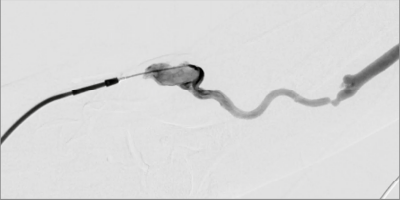

혈관조영술

수술이 아닌 시술,

정계정맥류 색전술

팔이나 사타구니 정맥을 통해 혈관 내로 진입하여

백금코일 및 경화제로 문제되는 혈관을 치료하는

안전하고 효과적인 인터벤션 시술입니다.